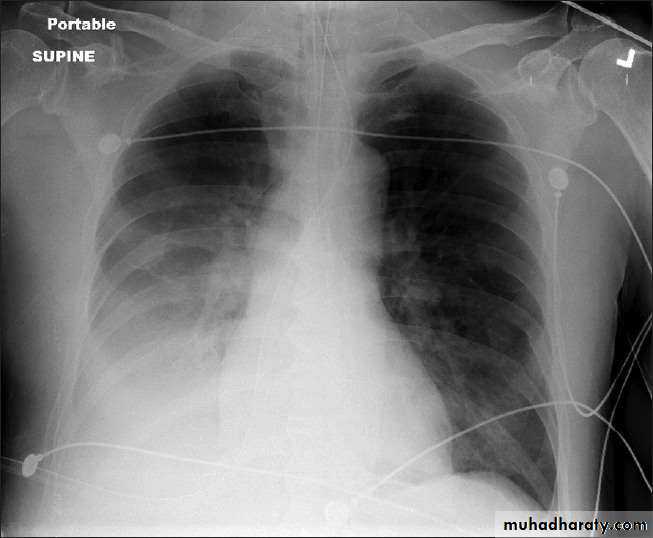

• INTERSTITIAL PNEUMONIA

• Peribronchovascular• Infiltrate

• Mycoplasma , viral